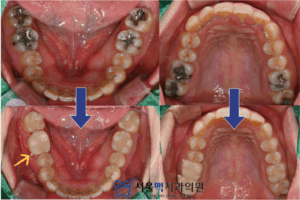

처음 내원하셨을 때 구강 내 촬영한 모습입니다.

화살표로 표시된 부분이 오래전에

아말감으로 충치치 료를 받으신 치아인데요.

아말감은 금속을 바탕으로한

재료로 시간이 지나면

부식되면서 색이 어둡게 변하는데요.

게다가 우식부분을 제거하고

아말감을 충전할 때,

접착제를 쓰지 않기때문에 사진에서처럼

일부가 조각으로 떨어져 나가는 경우도 있습니다.

환자분의 경우는

아말감으로 치 료한 아래치질이 검게 보이며

2차충치가 있으셨구요,

치아에 금이 간 부분도 있으셨어요.

이전에 아말감과 2차적으로

발생한 우식을 제거하였을 때,

범위가 컸기때문에 다시 떼우는(충전하는) 방식의

치료는 어려웠습니다.

그래도, 가능한 자연치질을 많이 남겨서

치료해드리기 위해 크라운(Crown)과

인레이(Inlay)로 충치치료를 마무리 해드렸는데요 ~

서울맥치과의 섬세함으로

전보다 자연스러운 치아색으로 마무리되어

환자분께서 몹시 기뻐하셨어요:)

노란색 화살표를 보시면,

크라운 보철물 볼쪽으로 작은 돌기가

나와있는 것을 보실 수 있는데요.

보철물이 완성되면 임시로

약 1주이상 사용해보시고 재부착해드리는데,

다시 재부착 하기위해 크라운을 빼는

문고리 같은것이라고 생각하시면 됩니다.

영구접착 해드릴 때는 제거해드리니

걱정하시마시고,

편하게 사용해보시고 말씀해주세요 🙂